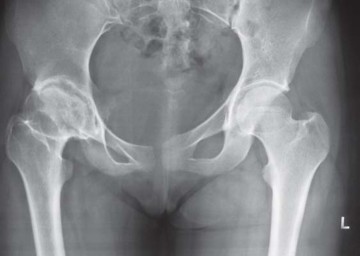

يُعد التهاب المفاصل التنكسي السبب الأكثر شيوعًا لألم مفصل الفخذ الذي يتطلب الجراحة. يحدث هذا عندما يتآكل الغضروف الواقي الذي يغطي نهايات العظام تدريجيًا، مما يؤدي إلى احتكاك العظام ببعضها البعض، مسببًا الألم والالتهاب والتيبس. غالبًا ما يرتبط هذا النوع من التهاب المفاصل بالتقدم في العمر، ولكن يمكن أن يحدث أيضًا نتيجة لإصابات سابقة أو تشوهات هيكلية.

النخر اللاوعائي لرأس الفخذ

يحدث النخر اللاوعائي عندما ينقطع إمداد الدم إلى رأس عظم الفخذ، مما يؤدي إلى موت الخلايا العظمية وانهيار رأس الفخذ. يمكن أن تسببه عدة عوامل، بما في ذلك استخدام الكورتيكوستيرويدات لفترات طويلة، والإفراط في تناول الكحول، وبعض الأمراض مثل الذئبة الحمامية الجهازية (SLE)، والكسور أو الخلوع التي تؤثر على إمداد الدم.

تُعد الأشعة السينية (X-rays) الأداة التشخيصية الأساسية لتصوير مفصل الفخذ. يُطلب عادة:

* صورة شعاعية أمامية خلفية (AP) للحوض مع كلا مفصلي الفخذ: هذه الصورة تسمح بتقييم شامل لكلا المفصلين، وتحديد مركز رأس الفخذ، وطول الساق، والإزاحة (offset)، ومستوى قطع عنق الفخذ المحتمل، وحجم الجذع.

* صورة شعاعية جانبية للمفصل المصاب مع تكبير 15%: لتوفير رؤية إضافية لهيكل المفصل وتخطيط الزرع.